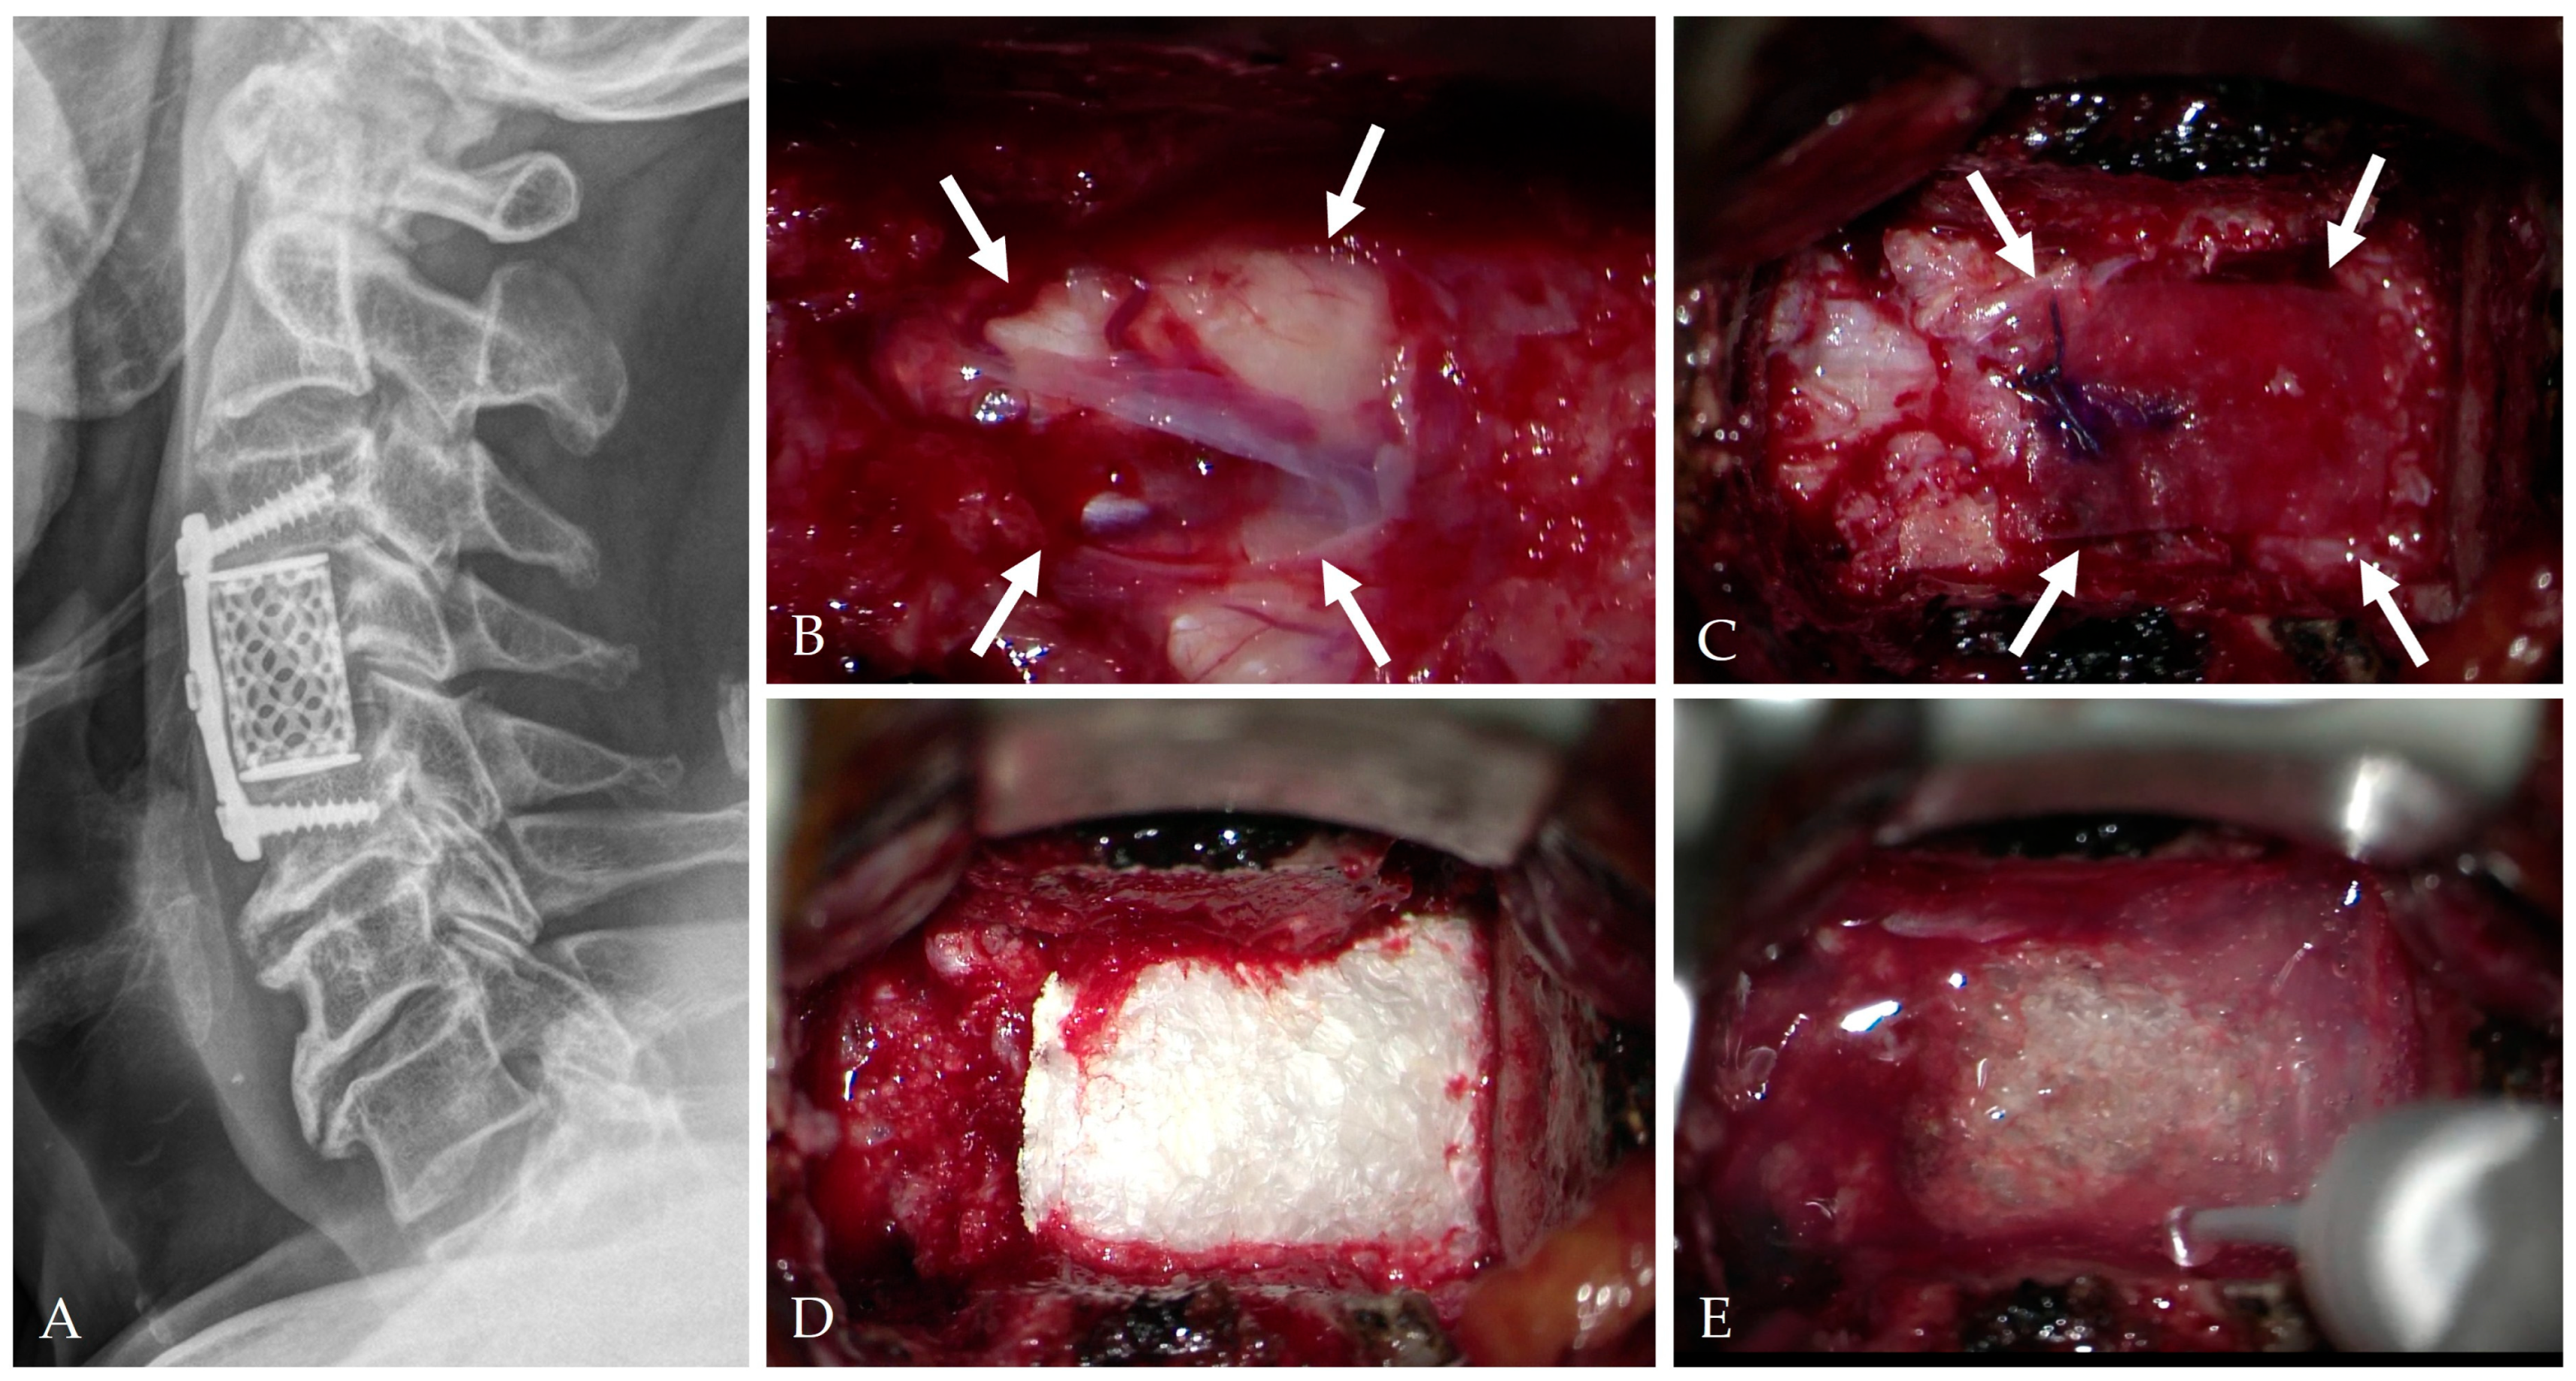

4. Intraoperative Repair Technique

4.1. Classification and Principles of Repair

4.2. Floating Repair and Dura-Preserving Techniques

4.3. Autologous Grafts and Biological Reinforcement

4.4. Artificial Dural Substitutes

4.5. Sealants and Adhesives

4.6. Composite “Sandwich” Repair

4.7. Controlled CSF Diversion

4.8. Vascularized Flap Reinforcement

- Mitchell, B.D.; Verla, T.; Reddy, D.; Winnegan, L.; Omeis, I. Reliable intraoperative repair nuances of CSF leak in anterior cervical spine surgery. World Neurosurg. 2016, 88, 252–259. [Google Scholar] [CrossRef]

- Chen, Y.; Guo, Y.; Chen, D.; Lu, X.; Wang, X.; Tian, H.; Yuan, W. Diagnosis and surgery of OPLL associated with dural ossification in the cervical spine. Eur. Spine J. 2009, 18, 1541–1547. [Google Scholar] [CrossRef]

- Lei, T.; Shen, Y.; Wang, L.F.; Cao, J.M.; Ding, W.Y.; Ma, Q.H. Cerebrospinal fluid leakage during anterior cervical spine surgery for severe OPLL: Prevention and treatment. Orthop. Surg. 2012, 4, 247–252. [Google Scholar] [CrossRef]

- Moon, J.H.; Lee, S.; Chung, C.K.; Kim, C.H.; Heo, W. How to address cerebrospinal fluid leakage following ossification of the posterior longitudinal ligament surgery. J. Clin. Neurosci. 2017, 45, 172–179. [Google Scholar] [CrossRef]

- Zhai, J.; Panchal, R.R.; Tian, Y.; Wang, S.; Zhao, L. Management of CSF leak after anterior cervical decompression surgery. Orthopedics 2018, 41, e283–e288. [Google Scholar] [CrossRef]

- Elder, B.D.; Theodros, D.; Sankey, E.W.; Bydon, M.; Goodwin, C.R.; Wolinsky, J.P.; Sciubba, D.M.; Gokaslan, Z.L.; Bydon, A.; Witham, T.F. Management of CSF leakage during ACDF and its effect on fusion. World Neurosurg. 2016, 89, 636–640. [Google Scholar] [CrossRef]

- Joseph, V.; Kumar, G.S.; Rajshekhar, V. Cerebrospinal fluid leak during cervical corpectomy for ossified posterior longitudinal ligament: Incidence, management, and outcome. Spine 2009, 34, 491–494. [Google Scholar] [CrossRef] [PubMed]